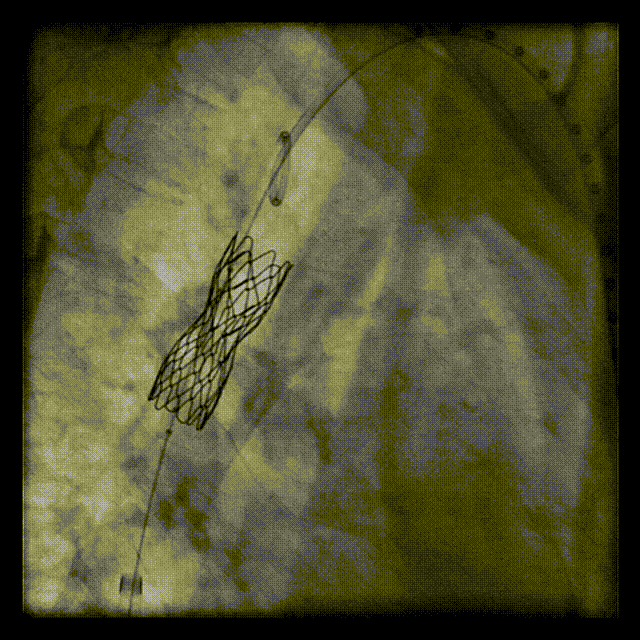

送入支架

造影定位

弓离断处送入39mm Cheatham-Platinum覆膜支架,选用20mmNuMED BiB球囊扩张

释放覆膜支架